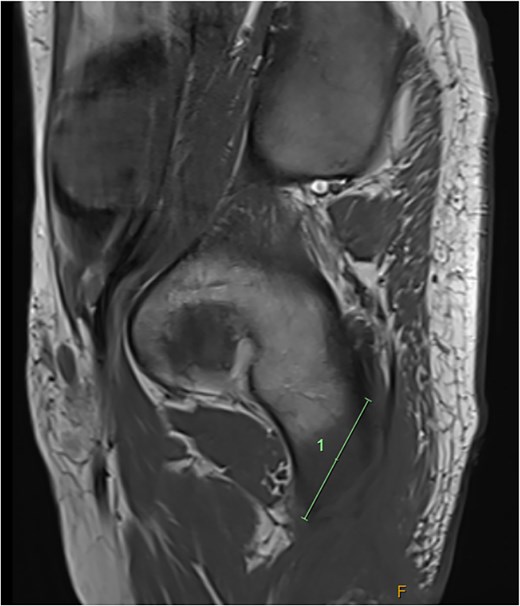

He was admitted to the Plastic and Reconstructive Surgery service for investigation and multidisciplinary management. Initial blood tests demonstrated mild anaemia, mildly elevated white cell count. His C reactive protein was 39. Liver and renal function tests were normal. Magnetic resonance imaging (MRI) demonstrated features of osteomyelitis within the left ischial tuberosity (Fig. 1) and bony involvement extending to the inferior pubic ramus (Fig. 2). Surgical biopsy was performed, with confirmation of osteomyelitis and deep tissue infection. Growth of staphylococcus epidermis and streptococcus anginous was demonstrated in pressure wound and bone chip samples.

Sagittal MRI imaging demonstrating bony signal changes extend to involve the inferior pubic ramus medially.